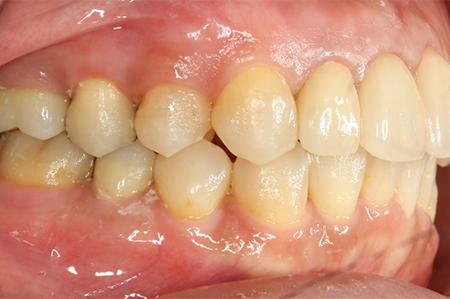

下の口腔内写真は初診時と矯正治療+補綴治療後のものになります。

虫歯が大きかった右上の奥歯も残すことが出来ました。

連結してあった前歯の被せ物(歯茎まで黒くなっている)も矯正後にきれいに治療することが出来ています。

歯並びが悪いと見た目が悪いだけではなく歯磨きがしづらく、噛み合わせが悪いことで力のかかり方が不均一になってしまい歯に亀裂が入り虫歯になりやすくもなります。

1本1本の歯にはそれぞれ役割があり、矯正治療を行うことでそれぞれの歯に適正な咬合力がいき渡るようにすることが出来、虫歯や歯周病になりづらい口腔内に、さらに審美的にもなります。